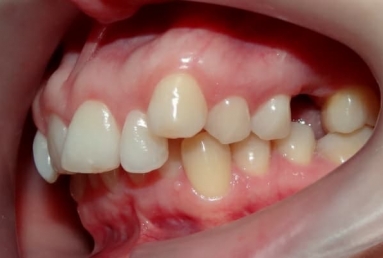

SAPPHIRE ORTHODONTIC DEVICE

Orthodontic treatment, external sinus lifting, dental implant and zirconium crown.